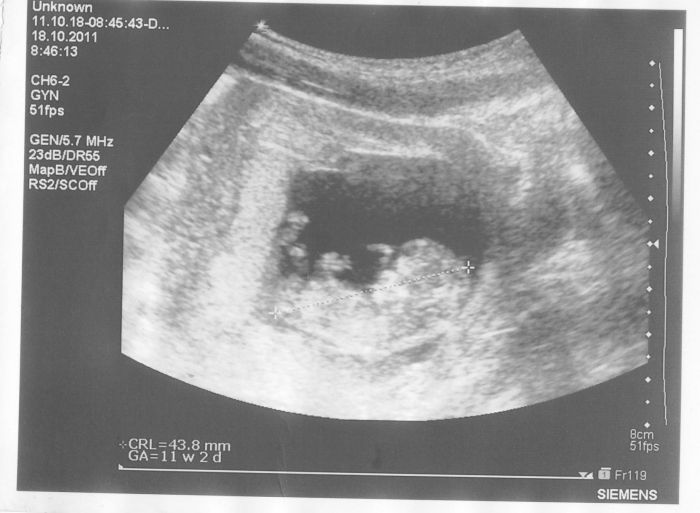

[42949] Ahoj ted jsem mu poslala sms že mám i výsledek ultrazvuku a že jsem v 11.týdnu, plus dva dny jsem mu už nepsala, ale už jsem skoro ve třetím měsíci, první trimestr mi bude pomalu končit. A už jsem viděla i první pohyby mávalo mi

Jo a změnila jsem fotku, jistě si všimnete že je tam už vidět hlavička, tělíčko, ručička ale tu druhou schovalo asi a nožička. Je to vidět hezky.ale až to bude větší bude to vidět lépe.

[43039] anebo možná i obě dvě nožičky jsou vidět tak co holky mám zatím hezký mimčo a prý je zdravý i srdíčko je ok.